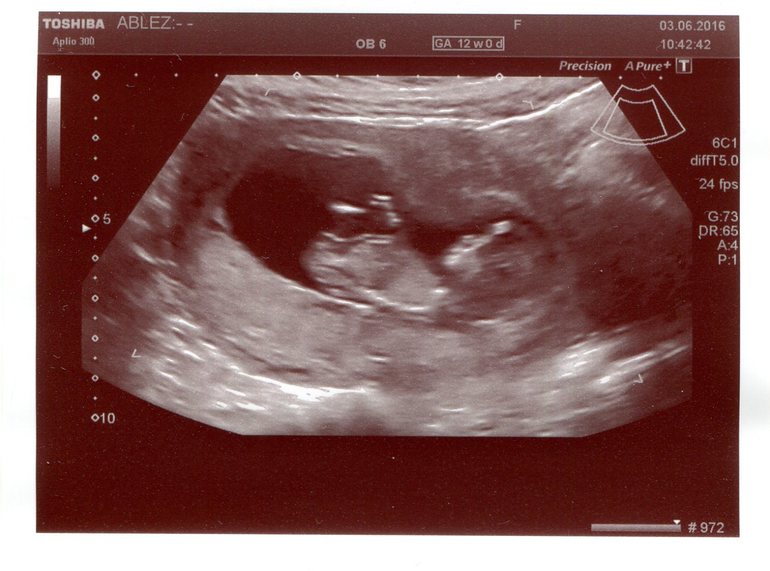

1й скиринг

сегодн я были на первом скирининге=) все хорошо=) врач предположил мальчика. но дома посмотрев на фото я чет мальчика не увидела. или это просто мне сильно хочется девочку кто -то может выдаст свои предположения тоже по бугорку? сенкс

Пупсичек какой! Я тоже в 12 нед. была на УЗИ, посмотрел, говорит половой бугорок, похоже на мальчика. А так девочку хочется))

Мне на первом скрининге по бугорку предположили мальчика, а на двух последних девочку. Так что не особо то доверяйте первому скринингу